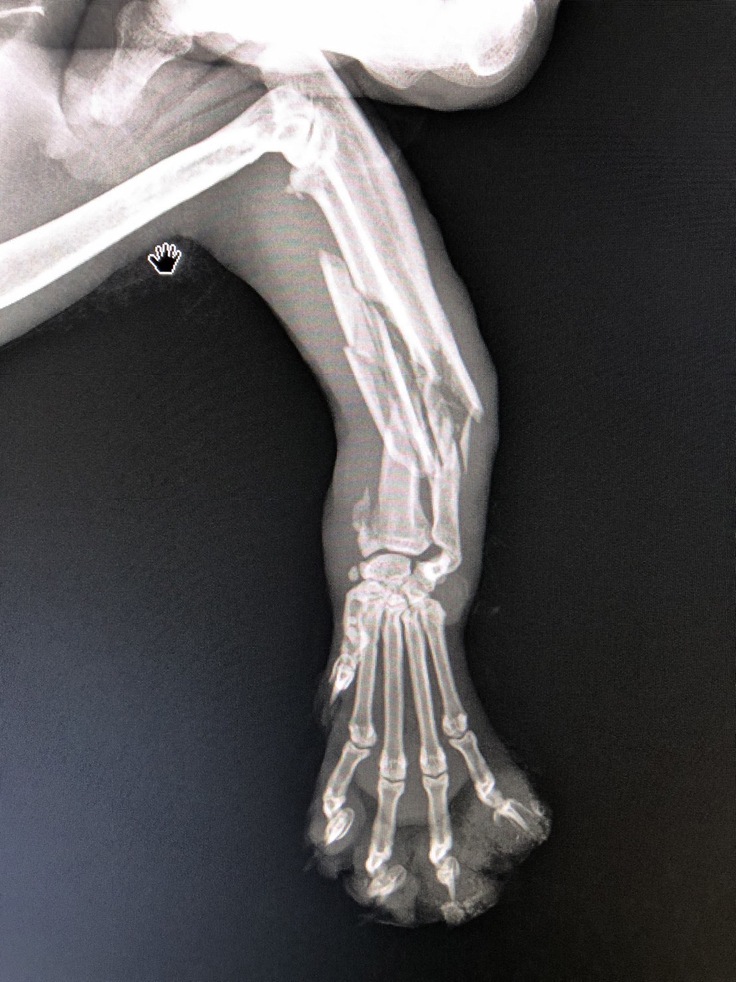

そして怪我をしている足は粉砕骨折していました。

異変があると感じていた指先はとくに怪我などはなく骨折で足がパンパンに腫れていたことと、引きずって歩いていたことでそう見えたのだろうとのこと。

レントゲン写真がこちらです。

足1本だけ粉砕骨折。内臓には特に損傷などはありませんでした。交通事故の可能性は低いかと思いますが原因は特定できませんでした。